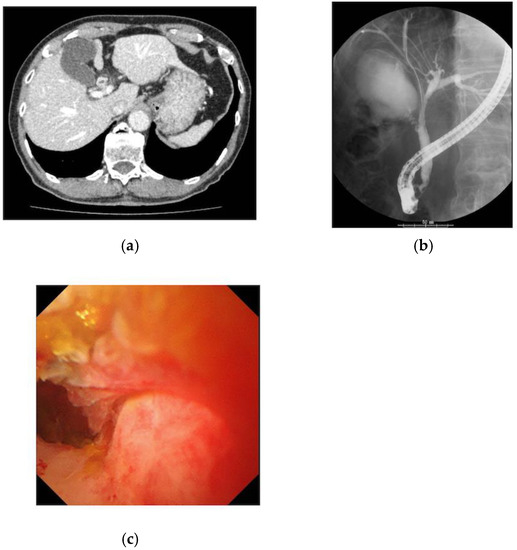

| Case | Age | Sex | Type of Cholangioscope | Endoscopic Diagnosis | Biopsy Obtained under Visualization | Surgical Operation | Final Diagnosis | Accuracy |

|---|---|---|---|---|---|---|---|---|

| 1 | 70 | M | CHF-B260 | Cholangiocarcinoma | N | Y | Cholangiocarcinoma | Y |

| 2 | 72 | M | SpyGlassDS | Cholangiocarcinoma | Y | Y | Cholangiocarcinoma | Y |

| 3 | 83 | M | CHF-B260 | IgG4SC | Y | Y | IgG4SC | Y |

| 4 | 72 | M | CHF-B260 | Compression by IPNB | N | Y | IPNB | Y |

| 5 | 77 | M | CHF-B260 | Inflammatory change | N | N | Inflammatory change | Y |

| 6 | 49 | F | SpyGlassDS | Inflammatory change | Y | N | Inflammatory change | Y |

| 7 | 49 | F | SpyGlassDS | Cholangiocarcinoma | Y | N | Cholangiocarcinoma | Y |

| 8 | 76 | M | SpyGlassDS | Cholangiocarcinoma | Y | Y | Cholangiocarcinoma | Y |

| 9 | 78 | M | SpyGlassDS | Cholangiocarcinoma | Y | Y | Cholangiocarcinoma | Y |

| 10 | 69 | F | SpyGlassDS | Cholangiocarcinoma | Y | Y | Cholangiocarcinoma | Y |

| 11 | 56 | M | SpyGlassDS | Cholangiocarcinoma | Y | Y | Cholangiocarcinoma | Y |

| 12 | 70 | F | SpyGlassDS | Cholangiocarcinoma | Y | Y | Cholangiocarcinoma | Y |

| 13 | 70 | M | SpyGlassDS | Cholangiocarcinoma | Y | Y | Cholangiocarcinoma | Y |

| 14 | 76 | F | SpyGlassDS | PSC | Y | N | PSC | Y |

| 15 | 78 | M | SpyGlassDS | IgG4SC | Y | N | IgG4SC | Y |